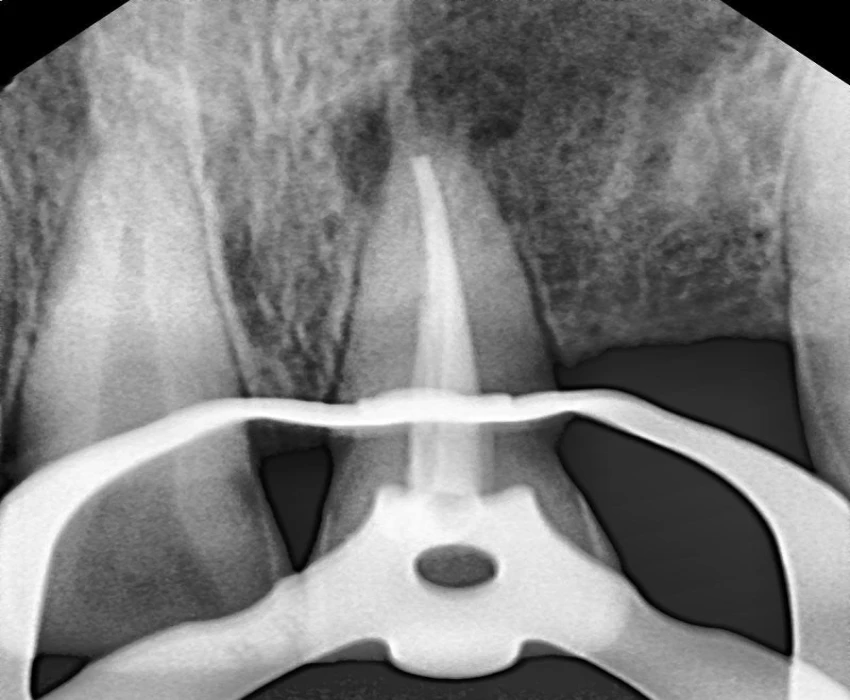

Investigation- CBCT, Viral markers, CBC, BT, CT

DIAGNOSIS- irreversible pulpitis with periapical granuloma.

TREATMENT- Faulty prosthesis is removed in respect to 22, with the help of tapered fissure. Access Opening is done' in respect to 21, under La. Working length is determined . Canals are prepared using Hyflex CM and obturated using Gutta percha using lateral condensation. Microperiosteal flap is raised. Window preparation irt 21 , periapical curretage apicoectomy is done irt 21 followed by retrograde filling with bioceramic. Cavity is filled with bone graft. Sutures placed.